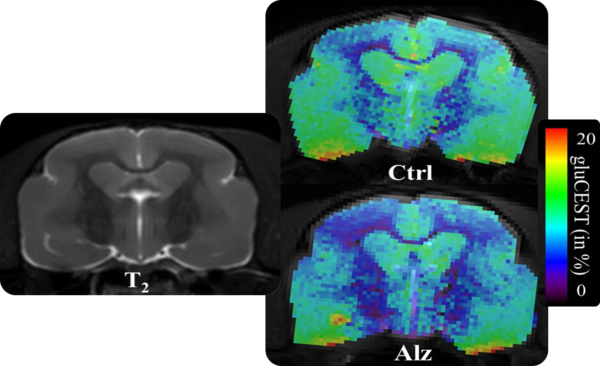

The advantages of ultra-high field combined with an expansive range of RF Coils for mice and rats

• Complete RF coil portfolio for mice and rats available, including coils for head, brain, cardiac, spine, body, multi-channel array coils with up to 8 channels, and x-nuclei

• Over 100 validated and ready to use in vivo protocols and scan programs for mice and rats

• MRI sequence portfolio of more than 1,000 sequence variations, including wireless cardiac imaging using navigator based IntraGate methods with cartesian or radial readout, as well as short echo time imaging, such as UTE and ZTE